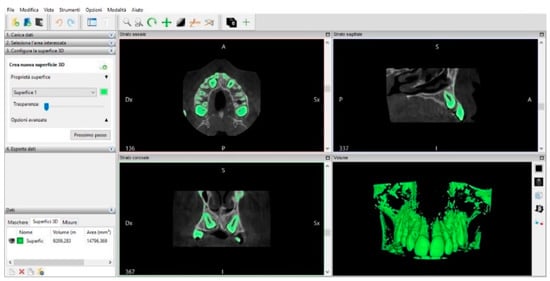

CBCT and Intra-Oral Scanner: The Advantages of 3D Technologies in Orthodontic Treatment

2. Materials and Methods